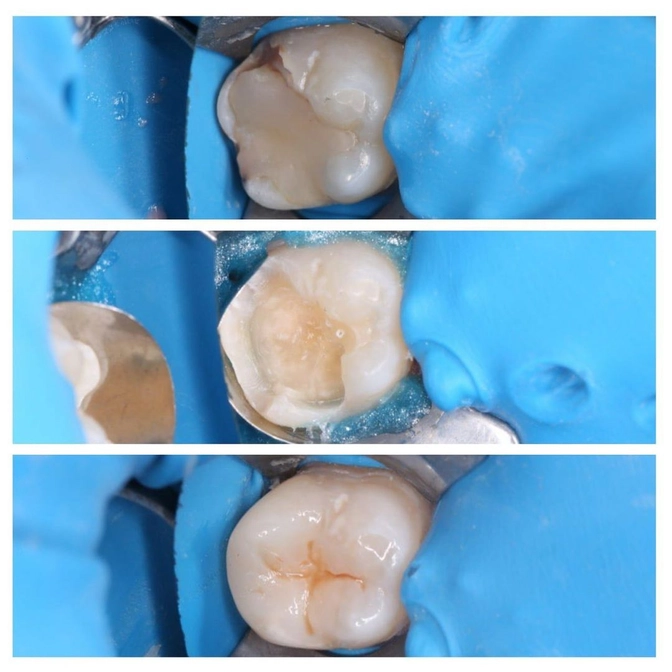

На фото взрослый пациент нашего стоматолога-терапевта Олеси Ибрагимовой.

Под пломбой начался кариозный процесс, видим, что ткани зуба начали чернеть.

Откладывать нельзя!

Иначе воспаление может уйти вглубь и поразить периодонт.

Что сделала доктор Ибрагимова?

✔️Старую пломбу убрала;

✔️Кариес вычистила;

✔️Полость обработала;

✔️Отреставрировала зуб пломбировочным материалом;

Эстетика и функциональность "семерки" восстановлена.